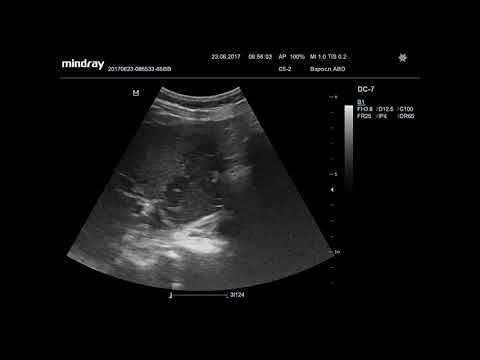

Ультразвуковая диагностика. Доктор Иогансен. Видеопримеры. Выпуск 7. Опухоль желчного пузыря.